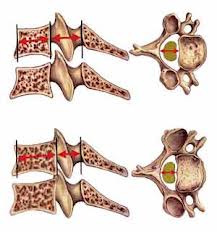

خار پاشنه یک مشکل شایع است که به دلیل فشار زیاد بر روی فاشیای پلانتار، محل اتصال آن به استخوان پاشنه، ایجاد میشود. این فشار میتواند منجر به کشیدگی و پارگیهای میکروسکوپی شود که باعث التهاب و درد در محل اتصال لیگامان به پاشنه میشود.